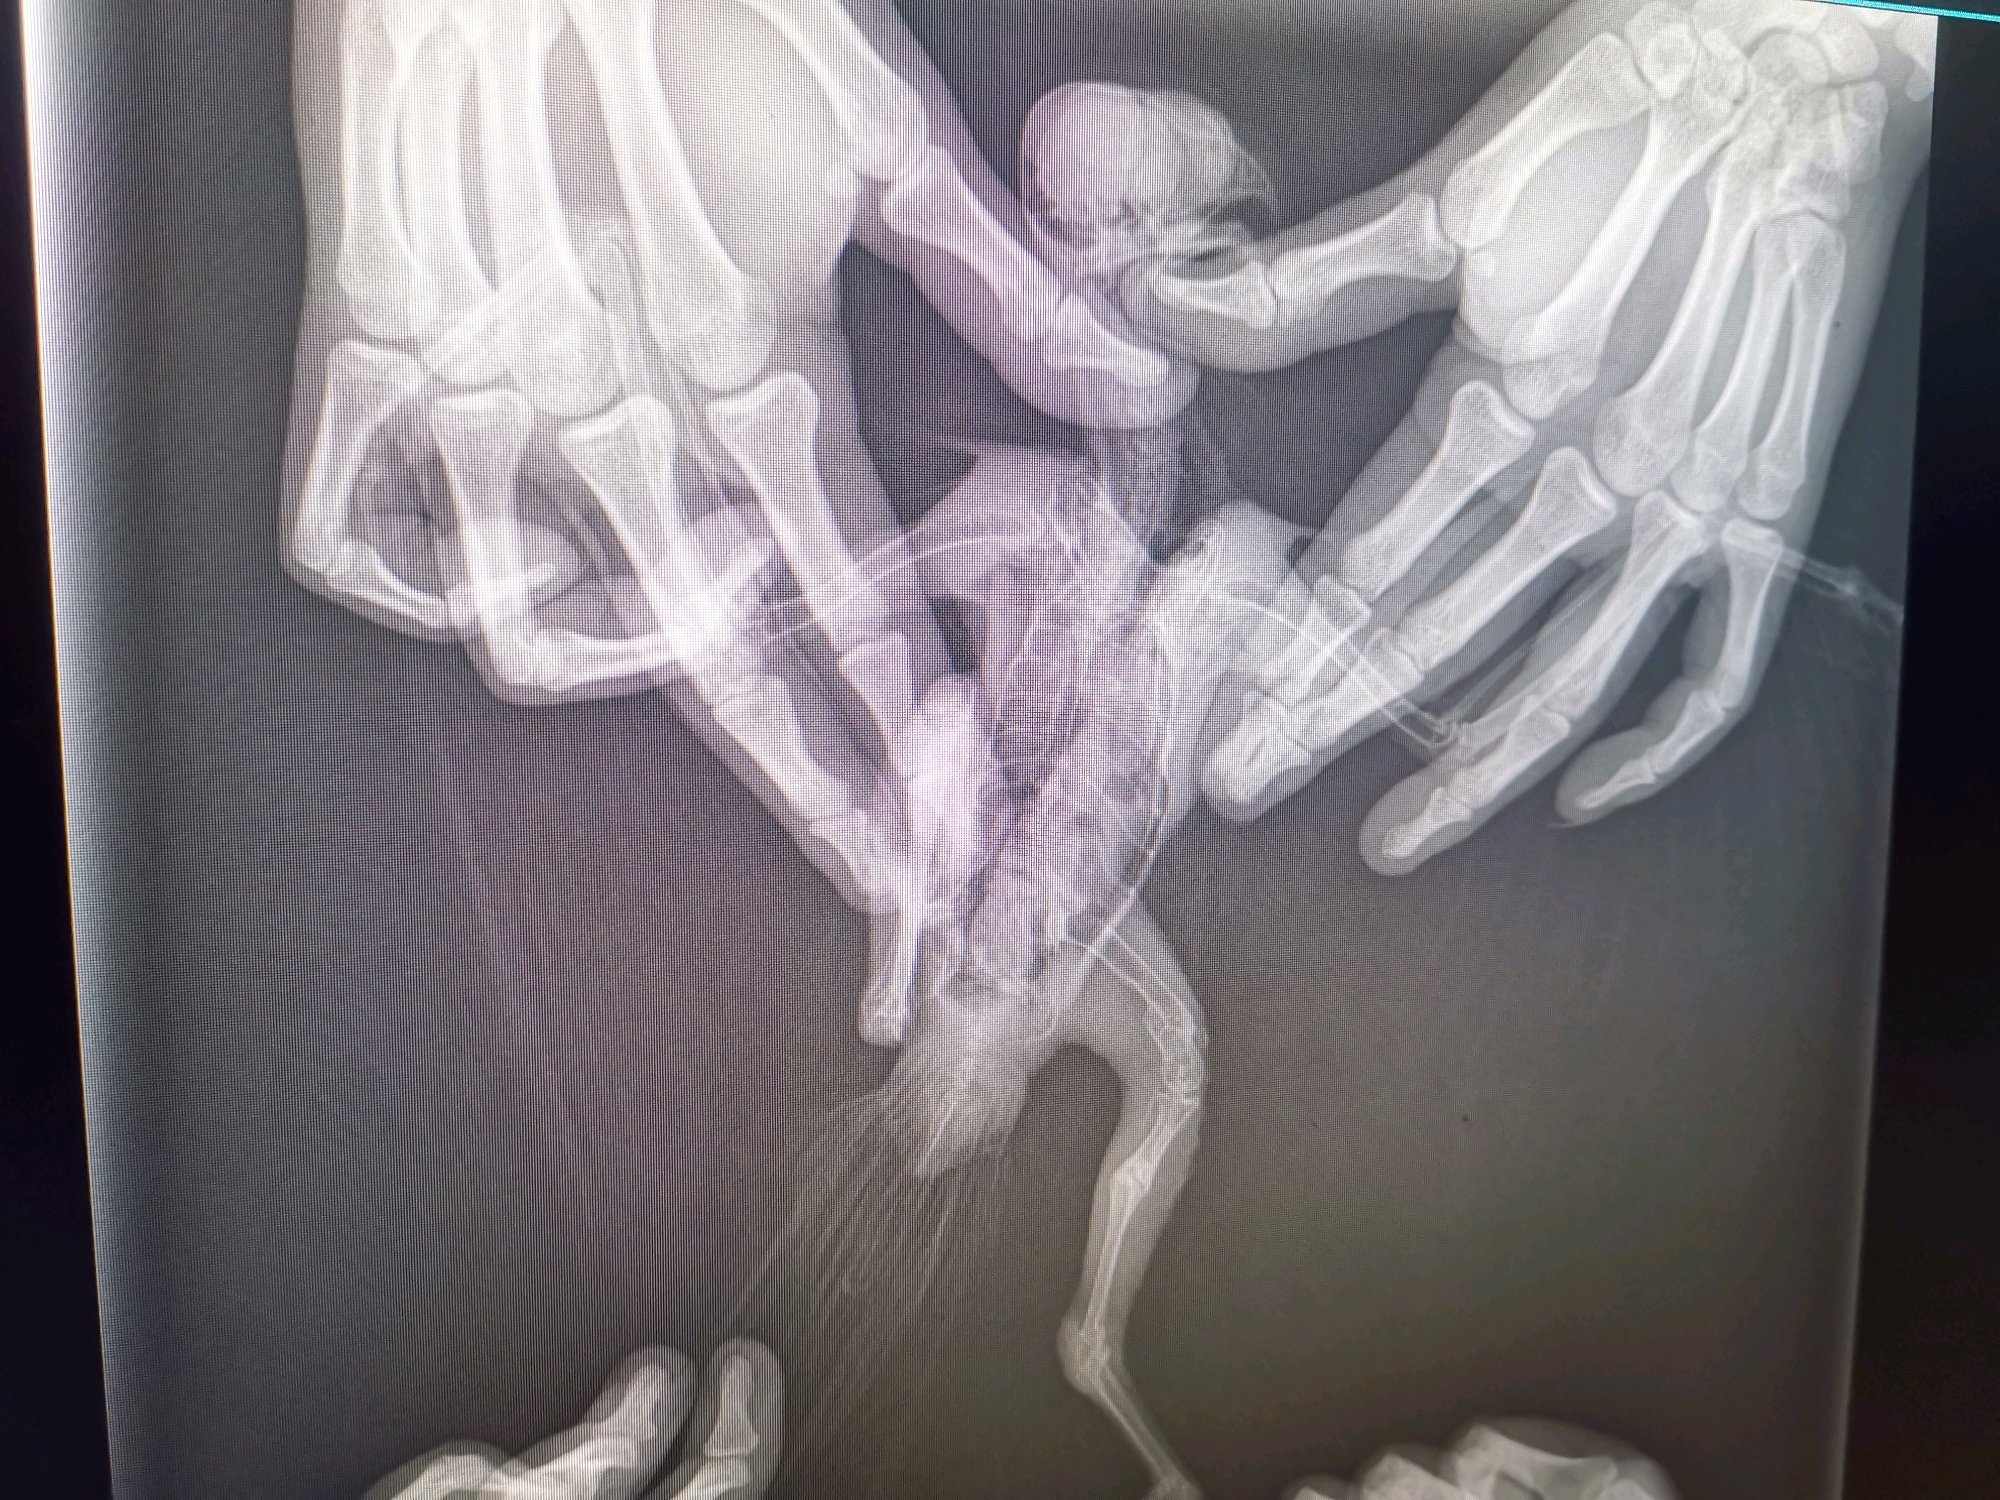

我是做通信的,因为基站拆迁,上面有鸟窝,等半天也没发现别的鸟来找他。他还小腿有点问题就救助他了。因为不懂,所以咨询了一个淘宝卖鹰具的一个人,他叫黑龙匠专业鹰隼用品,他说免费提供养护知识,还来看了我这红隼,我也是想治好他,那人说就是缺钙,我就给他喂钙片,确实好点了能站起来。但是也就到能站起来的程度了。我开始就怀疑不是缺钙,后来越来越这么觉得,我有点不相信他,问他好几次,他都说缺钙让我放心。后来我就到处找动物医院,拍片子显示那条腿有两处骨折,两个月了应该已经长好了,大夫说除非给腿两处敲折在接上,但是腿会短一块的不值得,鸟还要遭罪。说到这我真很怨这个淘宝商家,我都把鸟给你看了,要是早发现不至于这鸟一辈子都跛腿,一点没有责任心,都没仔细看,你要是仔细看,腿都鼓包了,我还好几次问你是不是腿有问题脱臼或者骨折。最后只能这样了,要求他赔偿或者别的也不可能,就是心疼这鸟。我也舍不得,但是总能看到这鸟在窗户向外望,他应该渴望自由。现在是没人干扰的情况下能站着,但是不稳。飞起来落地落到哪里,站不稳,扑腾一会才能站稳,有一条好腿,坏腿爪子能动,也有点力量。但是就是有点往外拐,大家可以看照片。请大家帮我看看,这还能放生嘛?我愿意养他一辈子,如果他开心自由我也可以放生,就怕他在外边活不了,不会打猎。请大家帮帮我。

以前腿折了,不知道。问一个淘宝卖鹰具的人他说是缺钙。让我喂钙片。鸟给他拿去了他都没好好看,给他发照片视频,他都没好好看。特别确定的告诉我就是缺钙,后来不信他去医院拍片子折了。那时候已经晚了。

我都去拍片子了。就是骨折了。我家红隼就是这么被人耽误的,误诊的。我要是不听早去拍片子就好了。